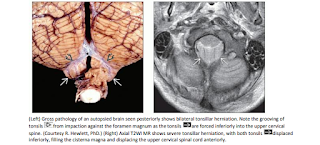

Head Emergency: Diagnostic Imaging (Click on image to magnify). Get link Facebook X Pinterest Email Other Apps - February 07, 2020 Get link Facebook X Pinterest Email Other Apps Comments